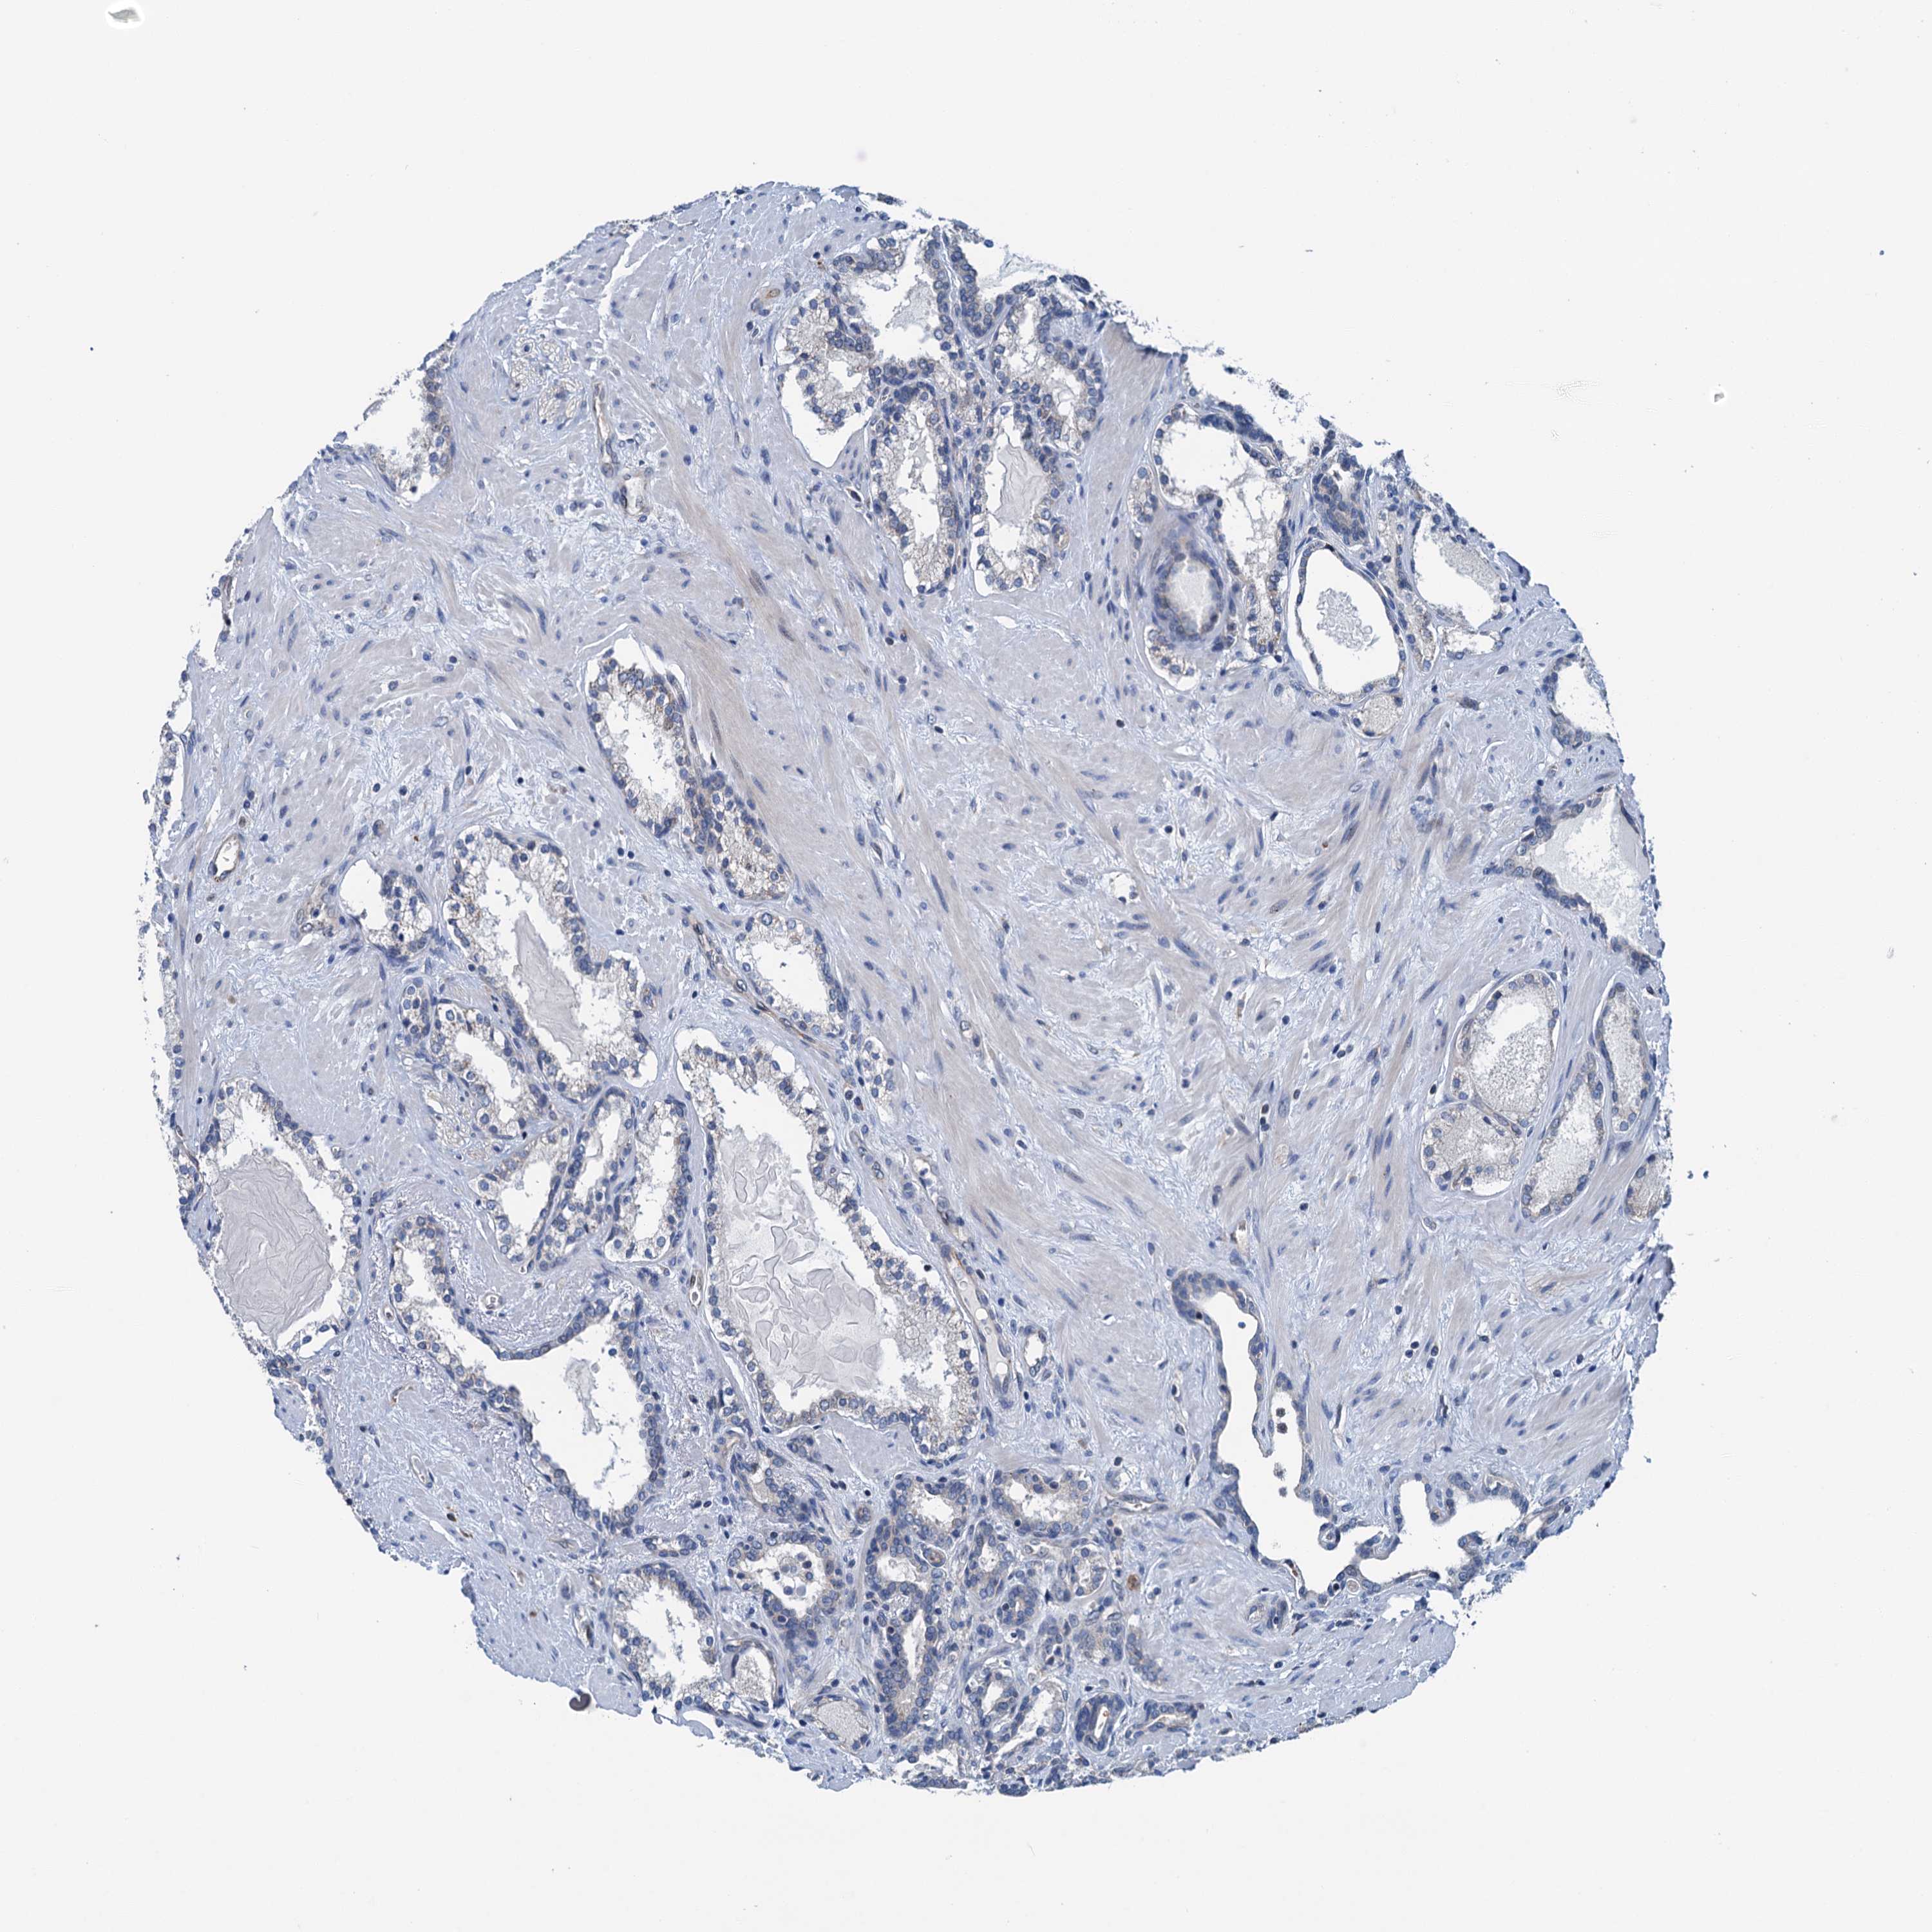

PROSTATE CANCER - Protein expressioni

A mouse-over function shows sample information and annotation data. Click on an image to view it in a full screen mode. Samples can be filtered based on level of antibody staining by selecting one or several of the following categories: high, medium, low and not detected. The assay and annotation is described here.

Note that samples used for immunohistochemistry by the Human Protein Atlas do not correspond to samples in the TCGA dataset.

Antibody stainingi

Antibody staining in the annotated cell types in the current human tissue is reported as not detected, low, medium, or high, based on conventional immunohistochemistry profiling in selected tissues. This score is based on the combination of the staining intensity and fraction of stained cells.

Each image is clickable and will lead to virtual microscopy that enables deeper exploration of all samples and also displays staining intensity scores, fraction scores and subcellular localization as well as patient and tissue information for each sample.

Antibody HPA040867

Staining

High

Medium

Low

Not detected

Intensity

Strong

Moderate

Weak

Negative

Quantity

>75%

75%-25%

<25%

None

Location

Nuclear

Cytoplasmic/membranous

Cytoplasmic/membranous,nuclear

Adenocarcinoma, NOS

Adenocarcinoma, High grade

Adenocarcinoma, Low grade